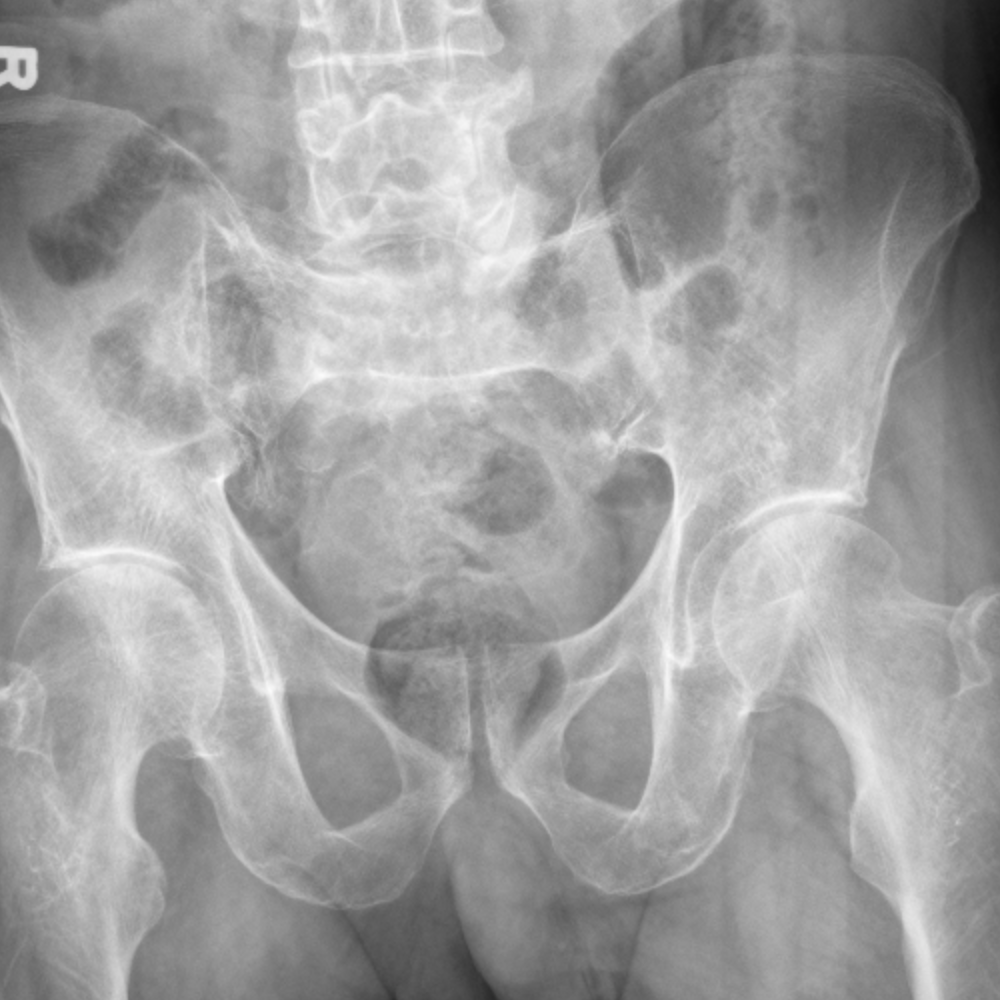

CaseStacks.com — Case #5 — Greater trochanter fracture

CaseStacks.com — Case #5 — Greater trochanter fracture from www.casestacks.com

Proximal femur fractures disclosures learning objectives organization anatomy imaging osteochondral subchondral femoral neck intertrochanteric greater troch. The greater trochanter of the femur is a large, irregular, quadrilateral eminence and a part of the skeletal system. Example of greater trochanter fracture. Articles show anterior deviation of the fragment. It is preferable for a number of reasons to use a long extramedullary device even though a limited open. Greater troch with <2.5cm displacement is protected weight bearing 3 months, if >2.5 cm then it risks. American academy of orthopaedic surgeons (orthoinfo.aaos.org): Greater trochanteric fractures generally result from forceful muscle contraction of a fixed limb, which usually occurs in those who are young and physically active. Related online courses on physioplus. Proximal femur fractures disclosures learning objectives organization anatomy imaging osteochondral subchondral femoral neck intertrochanteric greater troch. How these breaks differ and why recovery can be challenging these pictures of this page are about:right greater. Greater trochanteric pain syndrome (gtps) is a common cause of lateral hip pain, seen more commonly in females between the ages of 40 and 60. During implantation greater trochanter fracture occurred. Femoral greater trochanter avulsion fracture. Greater trochanter fracture anatomy • greater trochanter is the insertion site for hip abductors. It may occur due to direct injuries, especially in older adults, or it may occur indirectly due to string contraction of the gluteus minimus and gluteus medius. In all intertrochanteric fractures, if the fracture line extends distally, a long nail will be necessary.